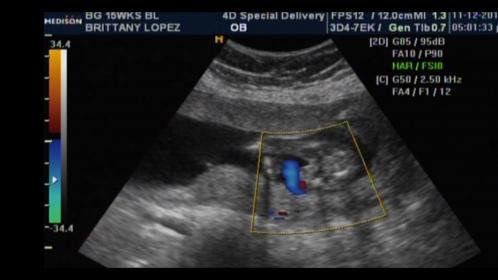

But I have had two scans, and told girl twice. Once the tech was extremely confident and said she wouldnt have said anything at all if she wasnt sure. The second tech said she was pretty sure she saw labia but our little one didnt want open her legs much at all that scan. I have pics from both scans that I want to post that include potty shots and nubs. Input?

Attachment 28271Attachment 28272Attachment 28273Attachment 28274